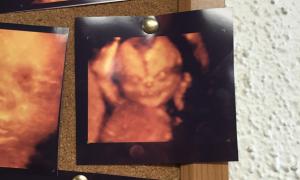

คู่สามีภรรยาช็อคหนัก!! หลังตัดสินใจอัลตร้าซาวด์แบบ4D แต่กลับเห็นลูกตัวเองหน้าคล้าย "ปีศาจ"

Tag:

เด็ก

ปีศาจ

อัลตร้าซาวด์

3D

20 ส.ค. 58 เวลา 14:51

guygodthedore